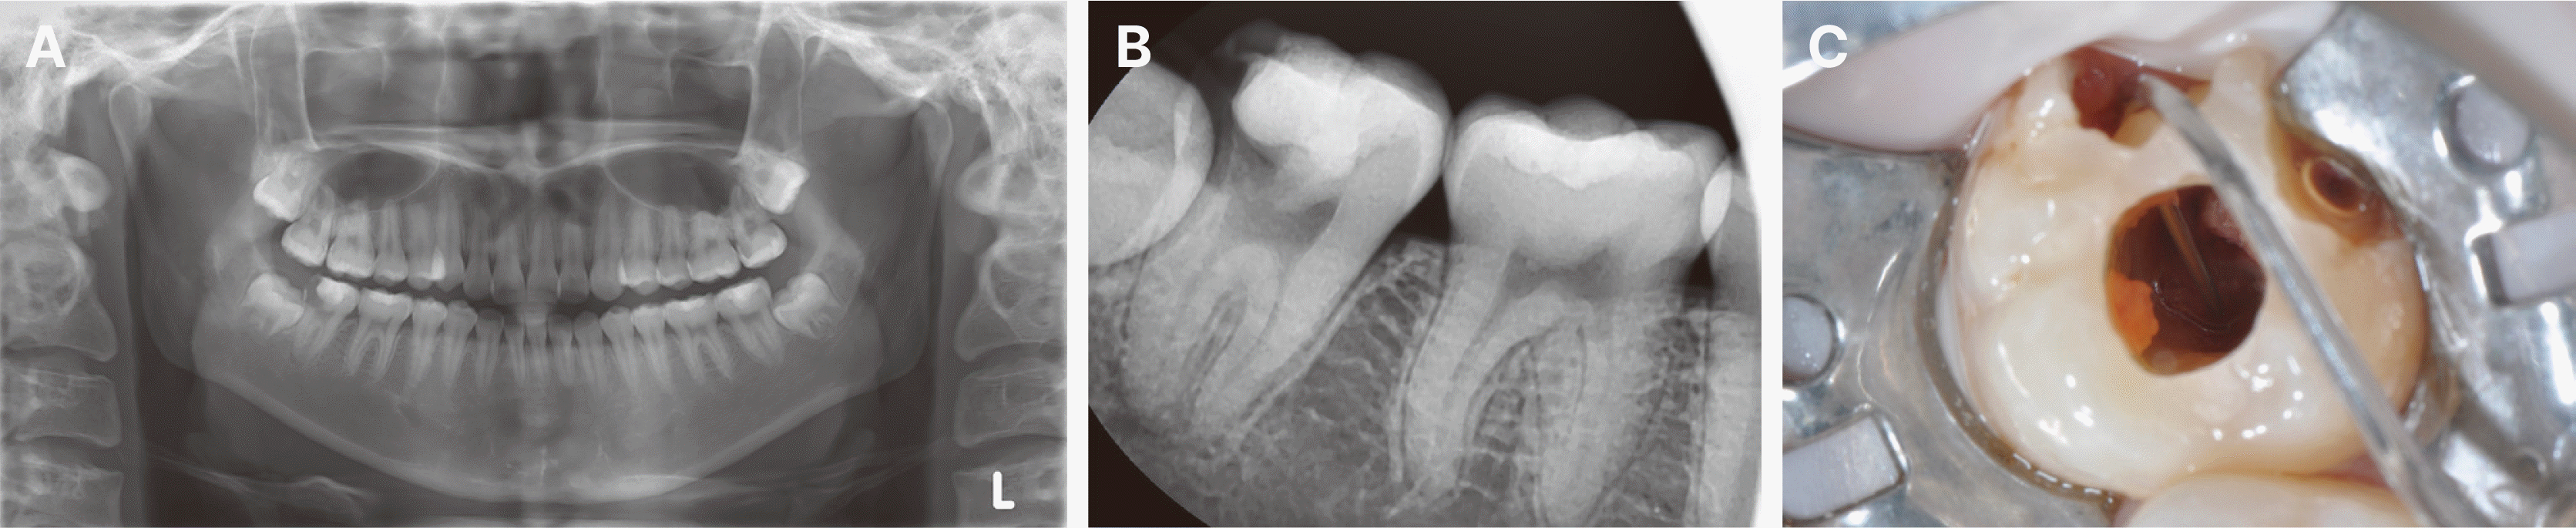

수술 10년 경과 후, 이식한 치아에 치수강 협착을 동반한 치근단 치주염이 발생하였다(Fig. 5A, 5B). 현미경 하에서 근관치료를 시행하였고 근관충전을 완료하였으며(Fig. 5C), 이후 리튬 다이실리케이트 크라운으로 최종 수복하였다(Fig. 5D). 크라운 수복 1년 후의 방사선 사진에서 안정적인 치근단 치유 양상이 관찰되었고(Fig. 6A, 6B), 수복 3년 후이자 이식 13년 경과 시점인 현재까지 치주낭 깊이 3 mm 이내, 동요도 1도 이하로 안정적인 상태를 유지하고 있다(Fig. 6C - 6E).

Fig. 5

Management of pulp canal obliteration and apical periodontitis under microscope at 10 years after transplantation. (A) Pre-operative panoramic radiograph showing pulp canal obliteration and apical periodontitis of the transplanted tooth. (B) Pre-operative periapical radiograph demonstrating detailed root canal anatomy and periapical lesion. (C) Postendodontic treatment radiograph showing complete root canal filling to the radiographic apex. (D) Periapical radiograph after lithium disilicate crown restoration showing adequate crown margin adaptation.

Fig. 6

Long-term follow-up after tooth transplantation. One-year follow-up after crown placement (11 years after transplantation) showing stable periapical healing and restoration: (A) Panoramic radiograph demonstrating normal bone density around the transplanted tooth, (B) Periapical radiograph showing complete healing of previous periapical lesion. Three-year follow-up after crown placement (13 years after transplantation) demonstrating successful long-term stability: (C) Panoramic radiograph showing maintained bone level, (D) Periapical radiograph confirming normal periodontal ligament space, (E) Clinical photograph showing healthy gingival condition and stable crown restoration.